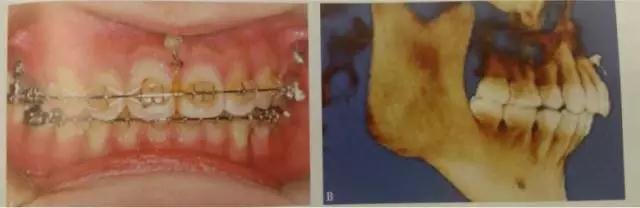

這是臨床上常見的應用方式,多用于需要強支抗內(nèi)收前牙,常種植于第二前磨牙與第一磨牙、第一磨牙與第二磨牙之間,應根據(jù)X線片觀察牙根間距離和鄰近解剖結構確定具體部位,采用微種植體一方面可以獲得支抗以盡可能內(nèi)收前牙,另一方面可整體內(nèi)收6個前牙而不擔心支抗問題,節(jié)省了調(diào)節(jié)時間。

頰側(cè)可以植于第二前磨牙和第一磨牙牙根間,第一磨牙頰側(cè)近遠中根、或第一磨牙和第二磨牙根尖之間。對于有些上頜合平面偏斜、單側(cè)后牙鎖結、個別后牙因?qū)涎廊笔Ф扉L等患者,可以考慮單側(cè)后牙區(qū)植入微種植體。對于前牙開合畸形,下頜缺乏縱合曲線,spee曲線過于平坦,雙側(cè)后牙正鎖合等情況。